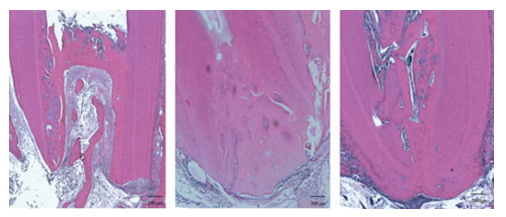

The apical part of the root includes three compartments: an apical cell-rich zone (where apical stem cells are mostly located and constitute a reservoir of undifferentiated pulp cells progenitors (abbreviated as SCAP by Sonoyama et al. [33]. Cells are located in the apical papilla mesenchyme, and in the radicular dental pulp [43- 50] (Figure 8-11).

Different apical closure types in group dental pulp cells + platelet rich plasma. Some bone-like tissue form a bridge and merge with cementum-like  tissue to close the apex.

Figure 8 : Different apical closure types in group dental pulp cells + platelet rich plasma. Some bone-like tissue form a bridge and merge with cementum-like  tissue to close the apex.